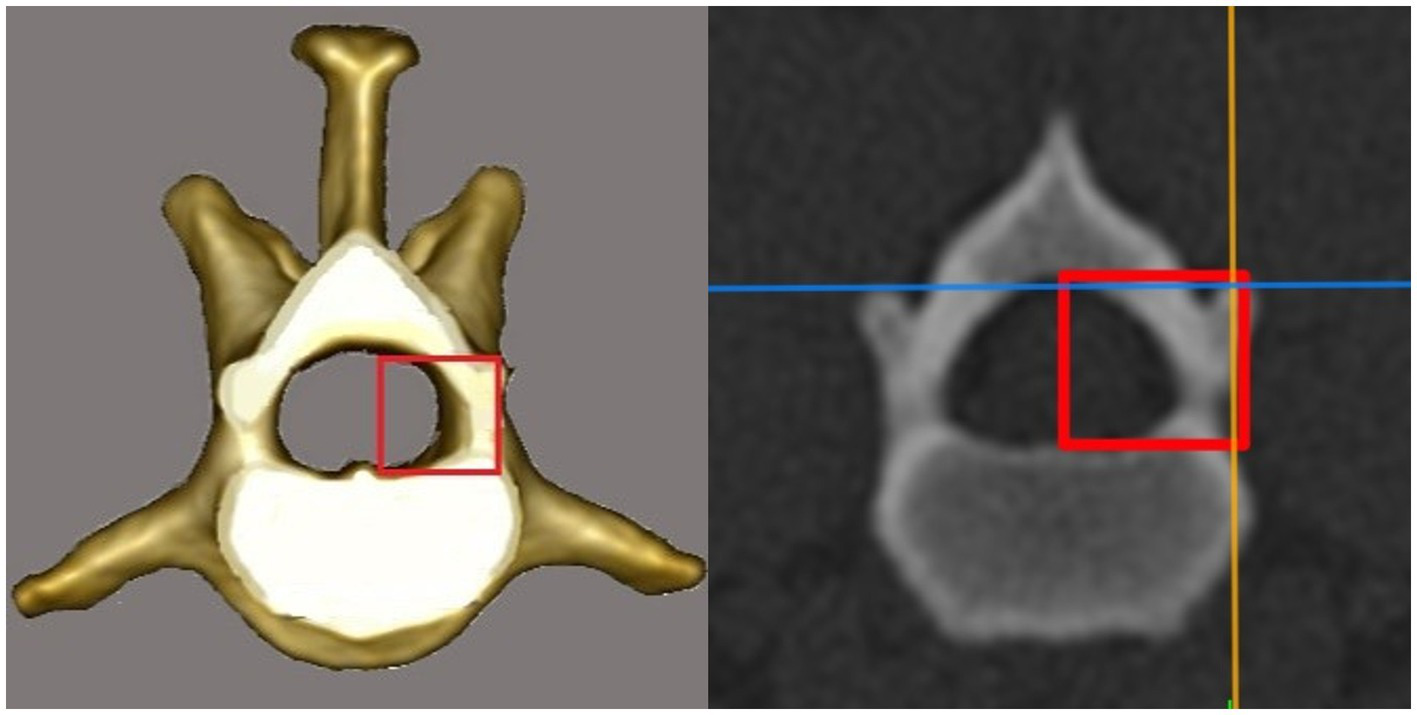

Figure 4

Drawing and CT image in the transversal plane. The vertical line of the red rectangle represents the distance between the dorsal border of the accessory process and the vertebral canal floor at the cranial end of the vertebral foramen.

the distance between the DBAP-VCF is defined as the distance in height between the DBAP at the cranial end of the vertebral foramen and the deepest point of the VCF (Figure 4);